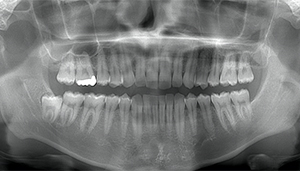

左下親知らずがたまに痛み、

できれば痛くなく抜きたい症例

- 抜歯前写真(レントゲン)

- 抜歯前写真(CT画像)

| 年齢 | 20代・女性 |

|---|---|

| 主訴 | 左下親知らずがたまに痛み、できれば痛くなく抜きたい |

| 親知らずの生え方 | 完全に埋まっている、横向きに生えている |

| 抜歯時間 | 50分 |

| 費用 | 約8,000円(保険診療、CT代含む) |

| 抜歯内容 | 左下親知らずが横向きになって半分埋まっている状態だったため、麻酔を行い、親知らずの奥の歯ぐきに切開をいれ、歯が囲んでいる骨を削り、歯の頭の部分を削って出し、その後根の部分に器具をかけて抜歯しました。 親知らずが一部神経に近い部分があったため、術後に麻痺が出る可能性がありました。このケースでは事前にCTを撮影し、歯の位置、根の方向、神経との距離を確認していたため、幸い麻痺が出ることはありませんでした。 術後1週間経過して糸取りをして治療は終了となりました。抜歯後3日間は腫れと痛みで大変だったが、糸取りをする頃には痛みも腫れも無くなったと患者さまも喜んでおられました。 |